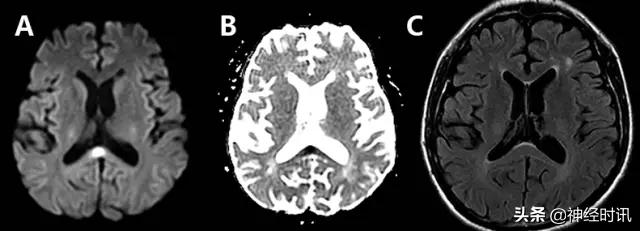

克雅氏病

克雅氏病(CJD)是由于朊蛋白错误折叠导致的快速进展性、传染性、致死性神经退行性疾病。DWI比FLAIR或T2WI更加敏感,并伴ADC降低。CJD患者有对称性基底节受累和对称性或非对称性皮层受累(图10)。

图10 一例48岁女性,精神状态改变、亚急性记忆减退伴步态异常1年,近期出现人格改变。MRI显示双侧基底节、丘脑、皮质弥散受限(A:DWI,B:ADC)和T2-FLAIR(C)高信号。患者被诊断为CJD。